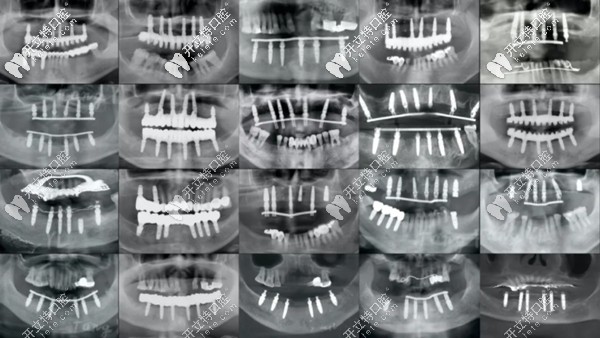

各類全口種植牙的全景片展示圖

(各類全口種植牙的全景片展示圖)

這么說吧,從上圖可以看出,即便同樣是全口種植牙,同樣是上下6顆種植體,同樣采用all-on-6即刻種植技術(shù),但用的植體長短、粗細(xì)不等。

其實(shí)它們也代表了不同品牌、規(guī)格、型號(hào)的植體,所以,價(jià)位也是不能一概而論的。